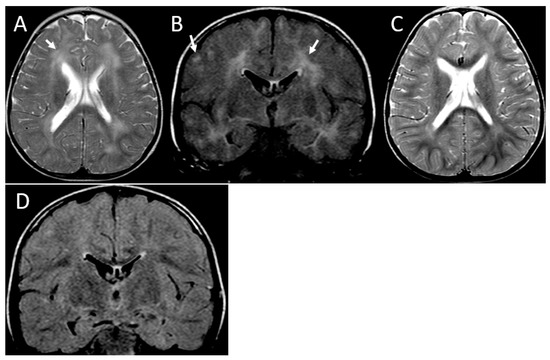

| Image Modality | Patient | 1 | 2 | 3 | 4 | 5 | 6 |

|---|---|---|---|---|---|---|---|

| Distribution | Diffuse/homogeneous | Patchy/asymmetric | Patchy/asymmetric | Patchy/asymmetric | Patchy/asymmetric | Patchy/asymmetric | |

| MRI at onset | Predominant location | Diffuse | Frontal and anterior temporal | Frontal and anterior temporal | Frontal and anterior temporal | Frontal and anterior temporal | Frontal and parietal |

| Infratentorial involvement | Pons | - | - | - | - | Pons | |

| Contrast enhancement | + | - | - | - | - | - | |

| MRI at follow up | Months after onset | 1st episode 8 mo (2 y 3 mo old) | |||||

| 2nd episode | |||||||

| 12 mo | 4 y | 10 mo | 24 mo | 13 y | 5 mo | ||

| (6 years old) | (6 years old) | (2 y 2 mo old) | (3 y 2 mo old) | (13 years old) | (20 mo old) | ||

| WM lesions improvement | Marked | Marked | Marked | Marked | Marked | Marked | |

| Brain Atrophy | Mild | - | Mild | - | - | - | |

| CT scan | Time after onset | 5 y | 4 y | 7 y | 1 mo | 13 y | 2 mo |

| Calcification | - | - | - | Basal ganglia | - | - |